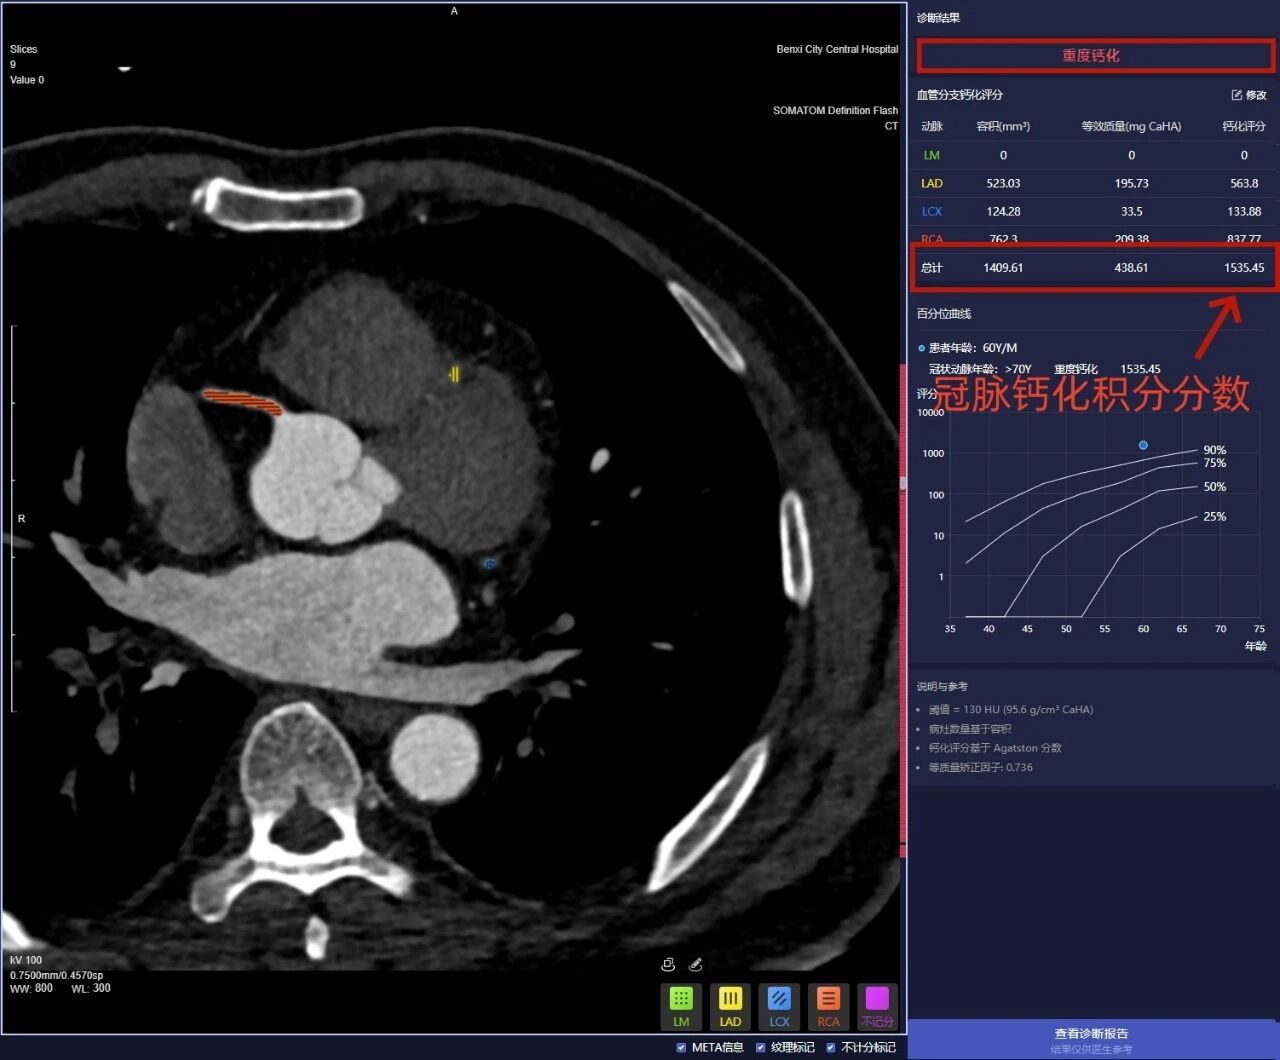

而冠脉钙化积分,就是通过 CT 给这些钙化斑块打分,分数越高,说明血管钙化越严重,心脑血管风险也越高,核心就是帮咱们早发现问题!

报告上的分数直接对应风险,记好这几个数,自己也能判断:

101—300 分: 重度钙化,中高风险,需警惕冠心病、心肌梗死,听医生安排进一步检查治疗;

≥ 300: 极重度钙化,高风险,血管可能已经严重狭窄,赶紧就医评估。